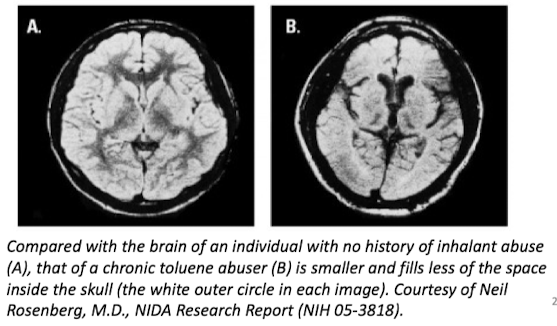

- ___ : model glues, correction fluids, lacquer thinners, plastic cements, spray paints (most characterized of volatile solvents)

• toluene

- neurotoxicity